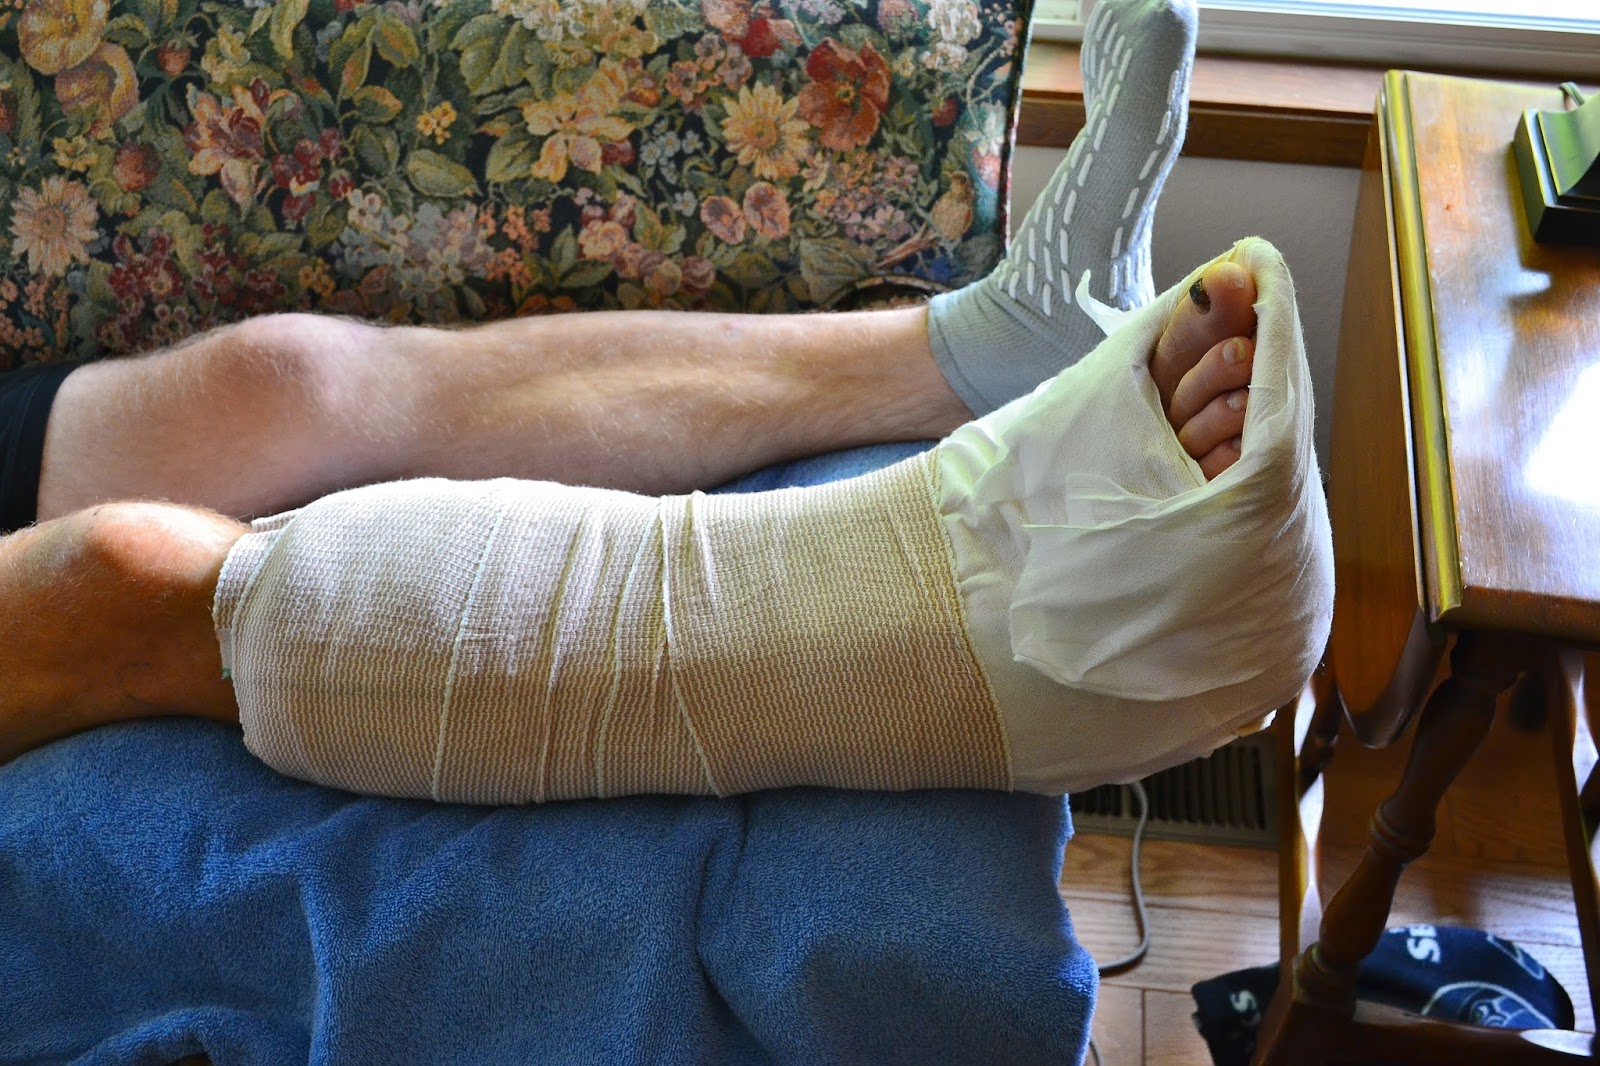

It was a long day at Harborview Medical Center, but Jake's ankle surgery went well this morning, an infusion of coffee eliminated a nasty headache in recovery this afternoon, and we have him home and installed on the couch now at 5:00.

What's at the core of all that wrap?

It's amazing how much metal they can put in to fix bones. I hope he has a swift and perfect recovery.